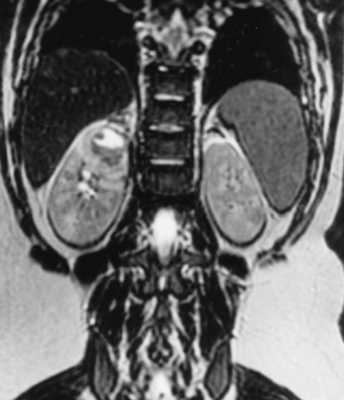

МРТ при пиелонефрите

Пиелонефрит - инфекция почек, возникающая в чашечно-лоханочной системе и паренхиме. Возбудителем является бактериальная инфекция, в том числе туберкулезная. Очень редко встречается грибковый пиелонефрит. Клиническая симптоматика острого пиелонефрита типична: острое начало с лихорадкой, боли в пояснице. Увеличение количества лейкоцитов и наличие бактерий в моче подтверждает диагноз. Попадает инфекция в почки ретроградным путем из нижних мочевых путей, а затем распространяется через чашечно-лоханочную систему в паренхиму почек, нарушая микроциркуляцию крови и приводя к ишемии. Обычно после клинического обследования пациентам назначают УЗИ, при котором лишь изредка удается найти изменения - локальные нарушения эхогенности паренхимы, скопления газа при эмфизематозном пиелонефрите и участки сниженной васкуляризации коры при дуплексном исследовании. Наиболее полезен метод при осложненном пиелонефрите - абсцессе, гидронефрозе, инфаркте почки. КТ без контрастирования также малочувствительна. После введения контраста при КТ можно увидеть участки отека со снижением плотности, между медуллярным и кортикальным веществом почки появляется полоска сниженного контрастирования (“кортикальный ободок”). Отмечается длительная задержка контраста в почке. При МРТ почки пиелонефрит проявляется в виде гиперинтенсивных участков на Т2-взвешенных МРТ. Также отмечается сниженное накопление контрастного вещества в пораженных участках при МРТ с контрастированием. Осложнениями острого пиелонефрита являются абсцесс ( при его прорыве с пиелонефрозом) и инфаркт почки. Изменение сигнала на диффузионно-взвешенных МРТ неспецифично, так как наблюдается и при почечно-клеточном раке.

МРТ почек. Корональная диффузионно-взвешенная МРТ. Инфаркт левой почки (стрелки).

Хронический приелонефрит - бактериальная инфекция почек, представляюший собой периодически возникающие обострения пиелонефрита. Инфекция затрагивает чашечки. При МРТ почек могут быть видны рубцовые изменения чашечек, почечная атрофия, истончение кортикального слоя почек, вторичное расширение чашечно-лоханочной системы. К редким вариантам хронического воспалительного процесса относится малакоплакия - представляющая собой воспалительный очаг по псевдоопухолевому типу. Малакоплакия отличается прогрессирующим течением и часто летальным исходом. При МРТ почек маоакоплакия выглядит как узлы 1-2 см низкой интенсивности сигнала на Т1- и Т2- взвешенных МРТ. Контрастирование при МРТ отмечается по отсроченному типу.

МРТ почек. Т2-взвешенная корональная МРТ. Абсцесс верхнего полюса правой почки.